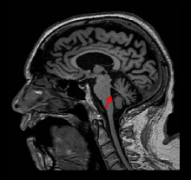

概述 帕金森是一种以震颤、运动减退、强直和姿势不稳为特征的神经系统综合征。较常见的原因为帕金森病(PD)(80%);其他神经退行性疾病包括皮质基底节变性(CBD),多系统萎缩...

帕金森病(PD)是一种神经退行性疾病,它影响大脑中控制运动的神经细胞。它会缓慢阻碍、损害或影响身体的运动。在疾病的早期阶段,副作用通常很小,仅限于震颤。然而,随着疾病的...